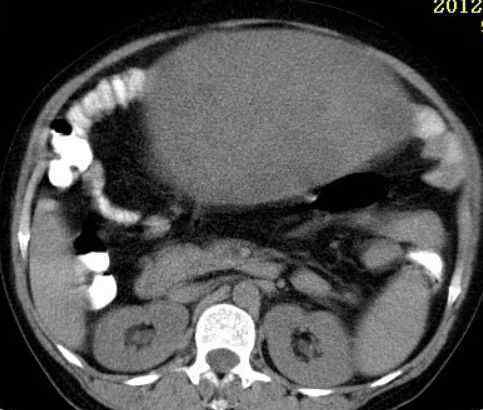

病史:女,51岁。没有任何不适,家人以为他们胖了。

病理结果:浆膜下子宫肌瘤(阔韧带肌瘤)

术中发现与左侧子宫壁、阔韧带关系密切,与左侧卵巢有粘连。

影像表现:

2.CT检查

大部分都是偶然发现的。子宫呈骨状,或子宫局部增厚,与子宫肌密度一致。变性时密度低,钙化时密度高。增强程度弱于子宫肌。

此例为巨大阔韧带肌瘤,易于诊断。